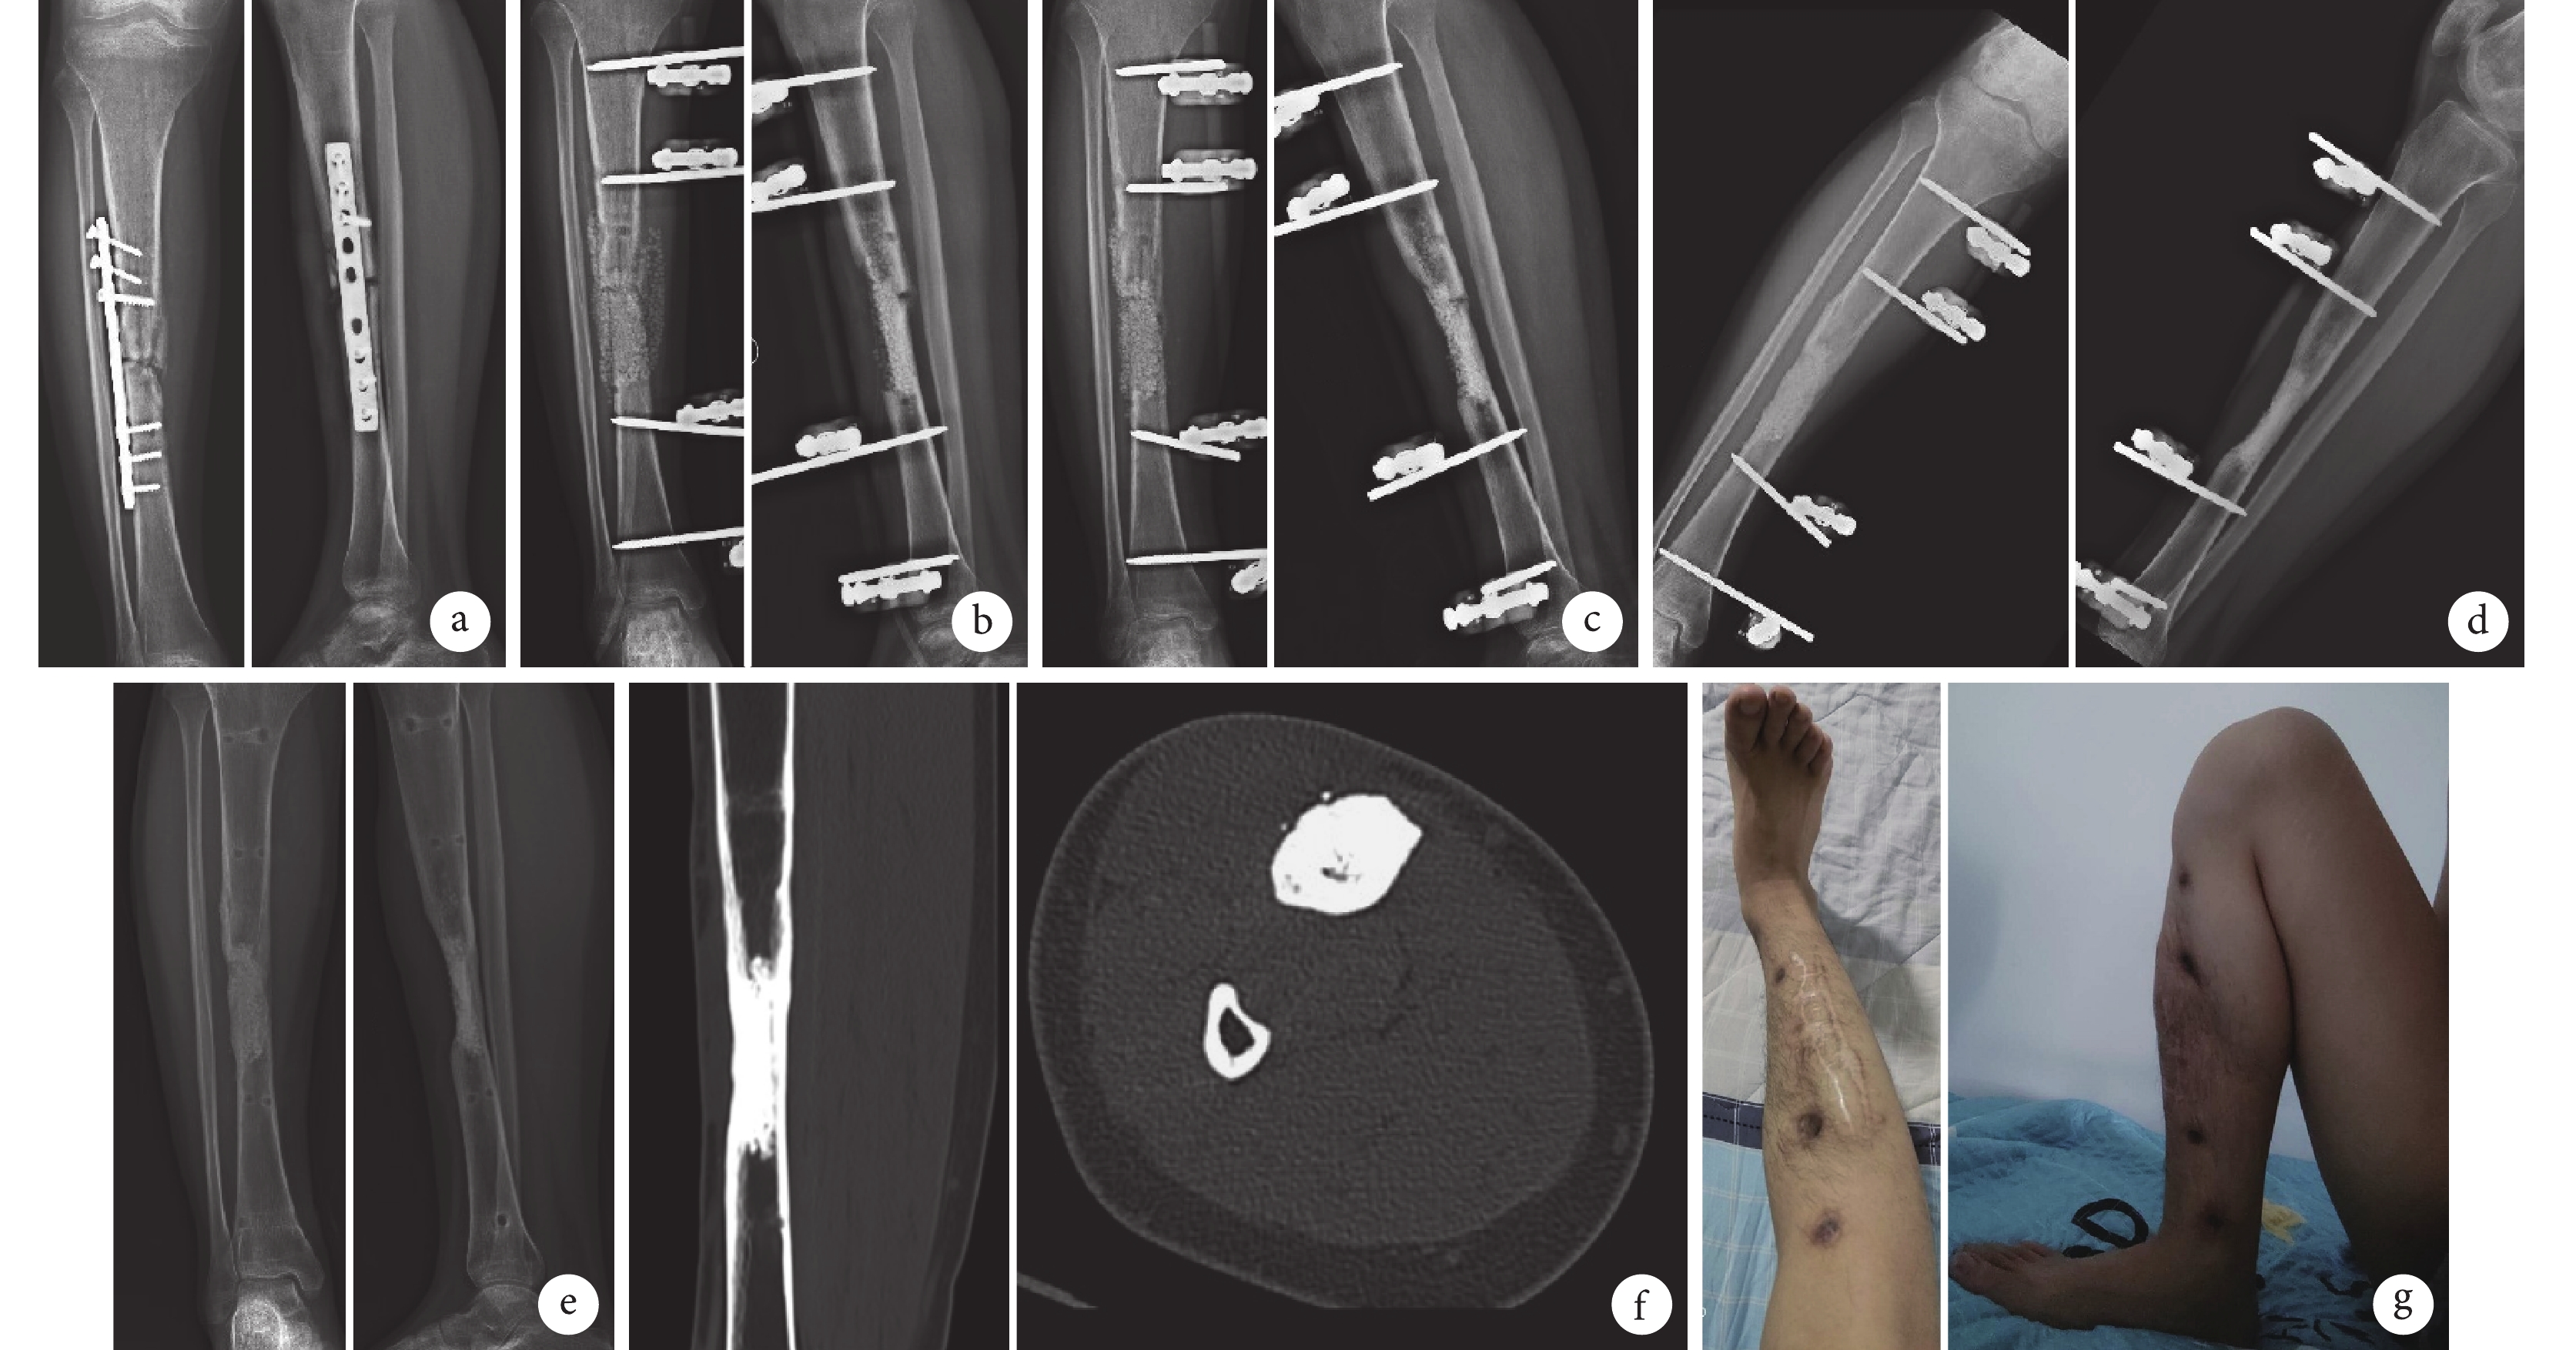

a. 術前正側位 X 線片;b. 術后 2 周正側位 X 線片示病灶清除并外固定,骨缺損區植入載 rhBMP-2 CPC 及載萬古霉素 CPC;c. 術后 6 個月正側位 X 線片示脛骨連續性基本恢復,CPC 顆粒被吸收及局部成骨;d. 術后 7 個月正側位 X 線片示骨缺損修復;e、f. 術后 12 個月正側位 X 線片及 CT 三維重建示脛骨骨折及骨缺損修復重塑;g. 術后 12 個月患肢功能恢復

Figure1. A 39-year-old male patient with osteomyelitis after internal fixation of right tibia fracture in the trial groupa. Preoperative anteroposterior and lateral X-ray films; b. Anteroposterior and lateral X-ray films at 2 weeks after operation showed that bone defect was repaired with CPC loaded with rhBMP-2 and vancomycin after clearing lesion and external fixation; c. Anteroposterior and lateral X-ray films at 6 months after operation showed that tibia continuity restored, and the CPC was absorbed and local osteogenesis; d. Anteroposterior and lateral X-ray films at 7 months after operation showed the bone defect was repaired; e, f. Anteroposterior and lateral X-ray films and CT three-dimensional reconstruction showed that the tibial bone defect was repaired and remodeled at 12 months after operation; g. The function of the affected limb recovered at 12 months after operation

試驗組 1 例脛骨骨髓炎切口出現無菌性滲液,經口服氯雷他定后愈合;兩組其余患者切口均Ⅰ期愈合。兩組各 1 例脛骨遠端骨髓炎復發,對照組 1 例肱骨骨髓炎復發,經再次清創植入載抗生素 CPC 后控制;其余患者骨髓炎均治愈。試驗組骨髓炎治愈率為 97.5%(39/40)、對照組為 95%(38/40),差異無統計學意義(χ2=0.000,P=1.000)。兩組修復骨容積及住院時間比較,差異均無統計學意義(P>0.05);X 線片及 CT 復查示兩組患者骨缺損均修復,其中試驗組術后 6 個月后骨連續性逐漸恢復,CPC 顆粒吸收明顯,誘導局部成骨,逐步骨質重塑、骨小梁結構重現,髓腔通暢及 CPC 誘導皮質骨形成;對照組術后 12 個月后骨連續性恢復,但 CPC 誘導成骨、骨質重塑及皮質化均明顯慢于試驗組。試驗組拆除外固定架時間及患肢完全負重時間均較對照組明顯縮短,差異有統計學意義(P<0.05)。見表2。典型病例見圖1、2。